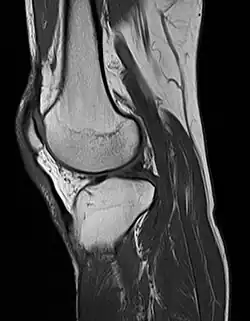

MRI of the knee

MRI uses strong magnetic fields to align atomic nuclei (usually hydrogen protons) within body tissues, then uses a radio signal to disturb the axis of rotation of these nuclei and observes the radio frequency signal generated as the nuclei return to their baseline states.[15] The radio signals are collected by small antennae, called coils, placed near the area of interest. An advantage of MRI is its ability to produce images in axial, coronal, sagittal and multiple oblique planes with equal ease. MRI scans give the best soft tissue contrast of all the imaging modalities. With advances in scanning speed and spatial resolution, and improvements in computer 3D algorithms and hardware, MRI has become an important tool in musculoskeletal radiology and neuroradiology.

One disadvantage is the patient has to hold still for long periods of time in a noisy, cramped space while the imaging is performed. Claustrophobia (fear of closed spaces) severe enough to terminate the MRI exam is reported in up to 5% of patients. Recent improvements in magnet design including stronger magnetic fields (3 teslas), shortening exam times, wider, shorter magnet bores and more open magnet designs, have brought some relief for claustrophobic patients. However, for magnets with equivalent field strengths, there is often a trade-off between image quality and open design. MRI has great benefit in imaging the brain, spine, and musculoskeletal system. The use of MRI is currently contraindicated for patients with pacemakers, cochlear implants, some indwelling medication pumps, certain types of cerebral aneurysm clips, metal fragments in the eyes, some metallic hardware due to the powerful magnetic fields, and strong fluctuating radio signals to which the body is exposed. Areas of potential advancement include functional imaging, cardiovascular MRI, and MRI-guided therapy.